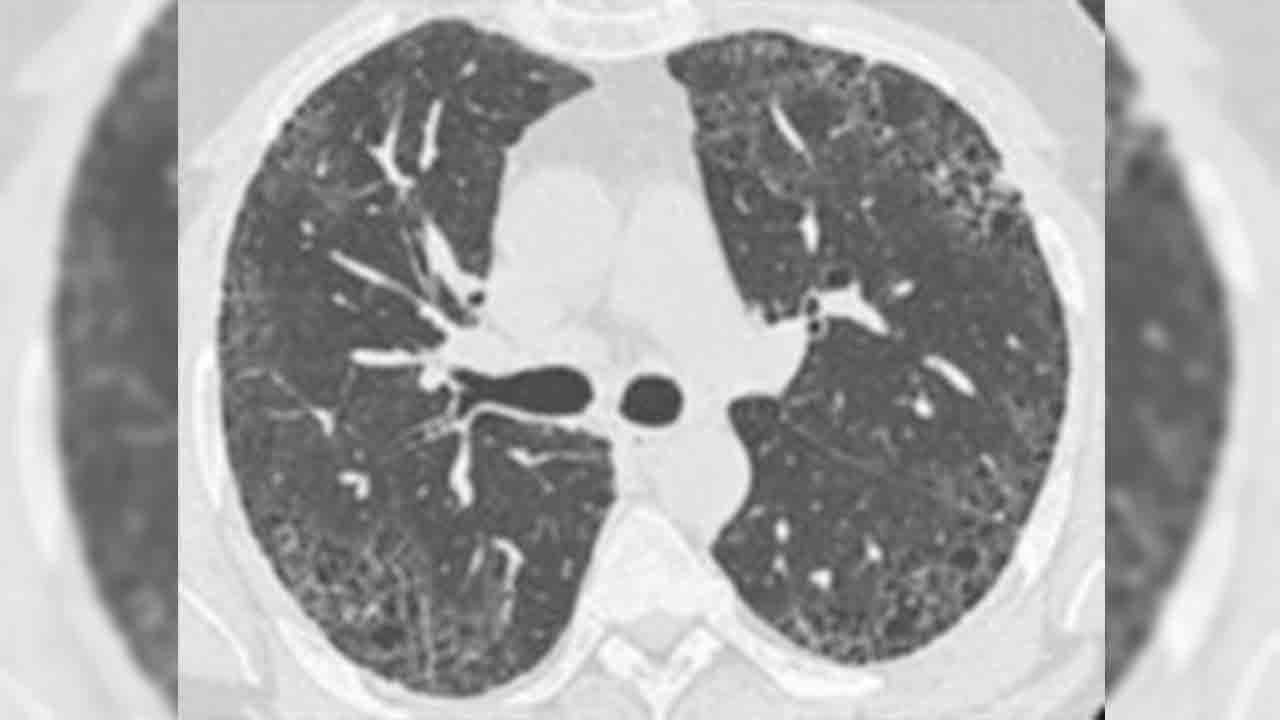

Demirci, pulmoner fibrozisin tanısal sürecinde tüm aşamaların eksiksiz yapılabilmesinin önemine dikkat çekerek, şu çağrıyı yaptı: “Uyum içinde çalışan multidisipliner ekiplerin olduğu merkez sayılarının artması önemli. Eğer bu merkezler artarsa, akciğer sertleşmesi hastalarının doğru tanı süreci kolaylaşır. Akciğer sertleşmesi tanı ve takibinde ayrıntılı solunum fonksiyon testleri, tekniğine uygun çekilen akciğer bilgisayarlı tomografisi ve romatolojik kan tahlilleri gerekir. Bunları doğru yapılabilen merkezlerin yaygınlaştırılması şart. Akciğer sertleşmesinde tedavi süreci sigaranın bırakılması, sertleşmeyi yavaşlatmaya yönelik- antifibrotik ilaçlar olan pirfenidon ve nintedanib kullanımı, oksijen tedavisi, pulmoner rehabilitasyon, aşılama, akciğer nakli ve yeni ilaç çalışmalarına hastaların yönlendirilmesi gibi çok yönlü bir süreci kapsar. Pulmoner rehabilitasyon ve akciğer nakli yapan merkezlerin yaygınlaştırılmasıyla akciğer sertleşmesi bulunan hastaların bu imkanlara rahatlıkla ulaşabilmesi sağlanabilir.”